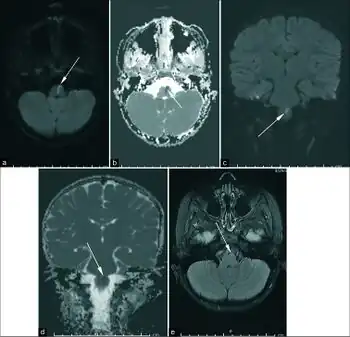

a-e)Axial diffusion-weighted imaging (DWI)- these findings support the clinical diagnosis of medial medullary syndrome aka Dejerine syndrome